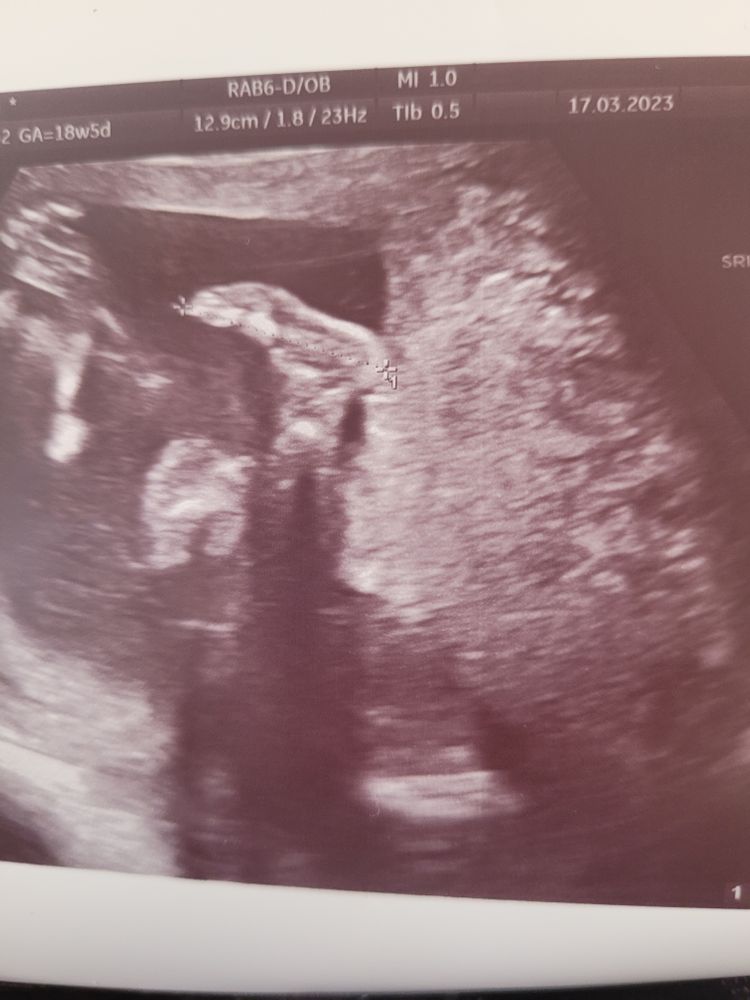

Узи 18+5. Низкая плацента. Кто что знает ?!!!

17.03.2023